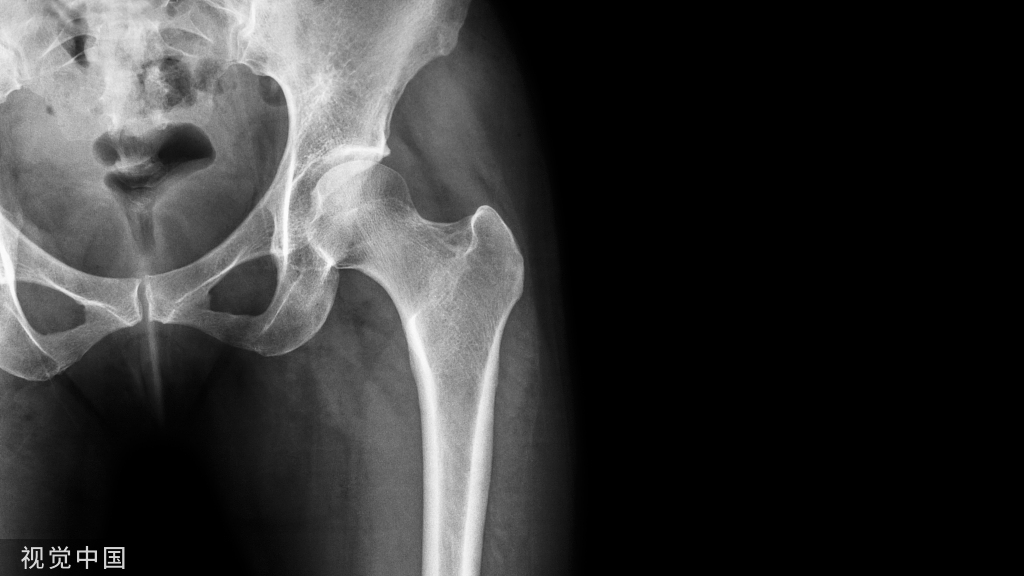

这些腕与手的骨折X线片如果没有标注箭头,你还能识别出来吗?

X线读片是骨科医生的基本功。

今天是腕部与手的X线片。所有X线片都

带有标注和说明

,可以选择长按图片,

自动翻译相关说明

。

进阶篇